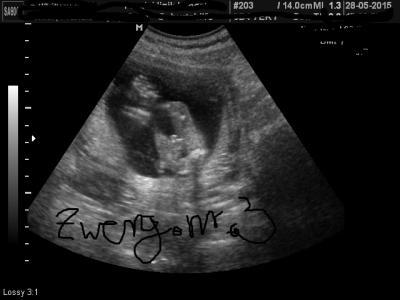

zwerg.nr.3

Schaut mal bitte was Ihr meint... LG Franzi

Bild zu Junge oder Mädchen? - Schwanger - wer noch? Rund um die Schwangerschaft

Sieht nach nem Jungen aus :-)

sieht nach nem Jungen aus ... :) würde sagen: sieht aus wie bei uns beim US ... :-D und das auch noch am gleichen Tag .. hihi LG Franzi

für mich eindeutig ein Junge

Würde auch sagen ein Junge, bei meinem zweien sah es auch so aus ;D